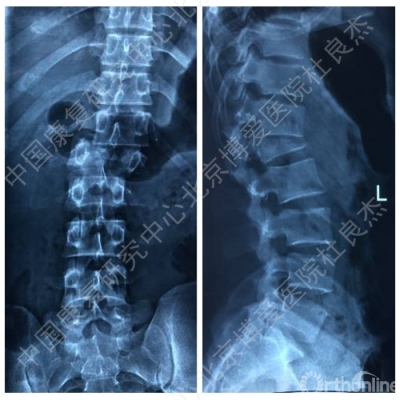

X线片

CT及三维重建